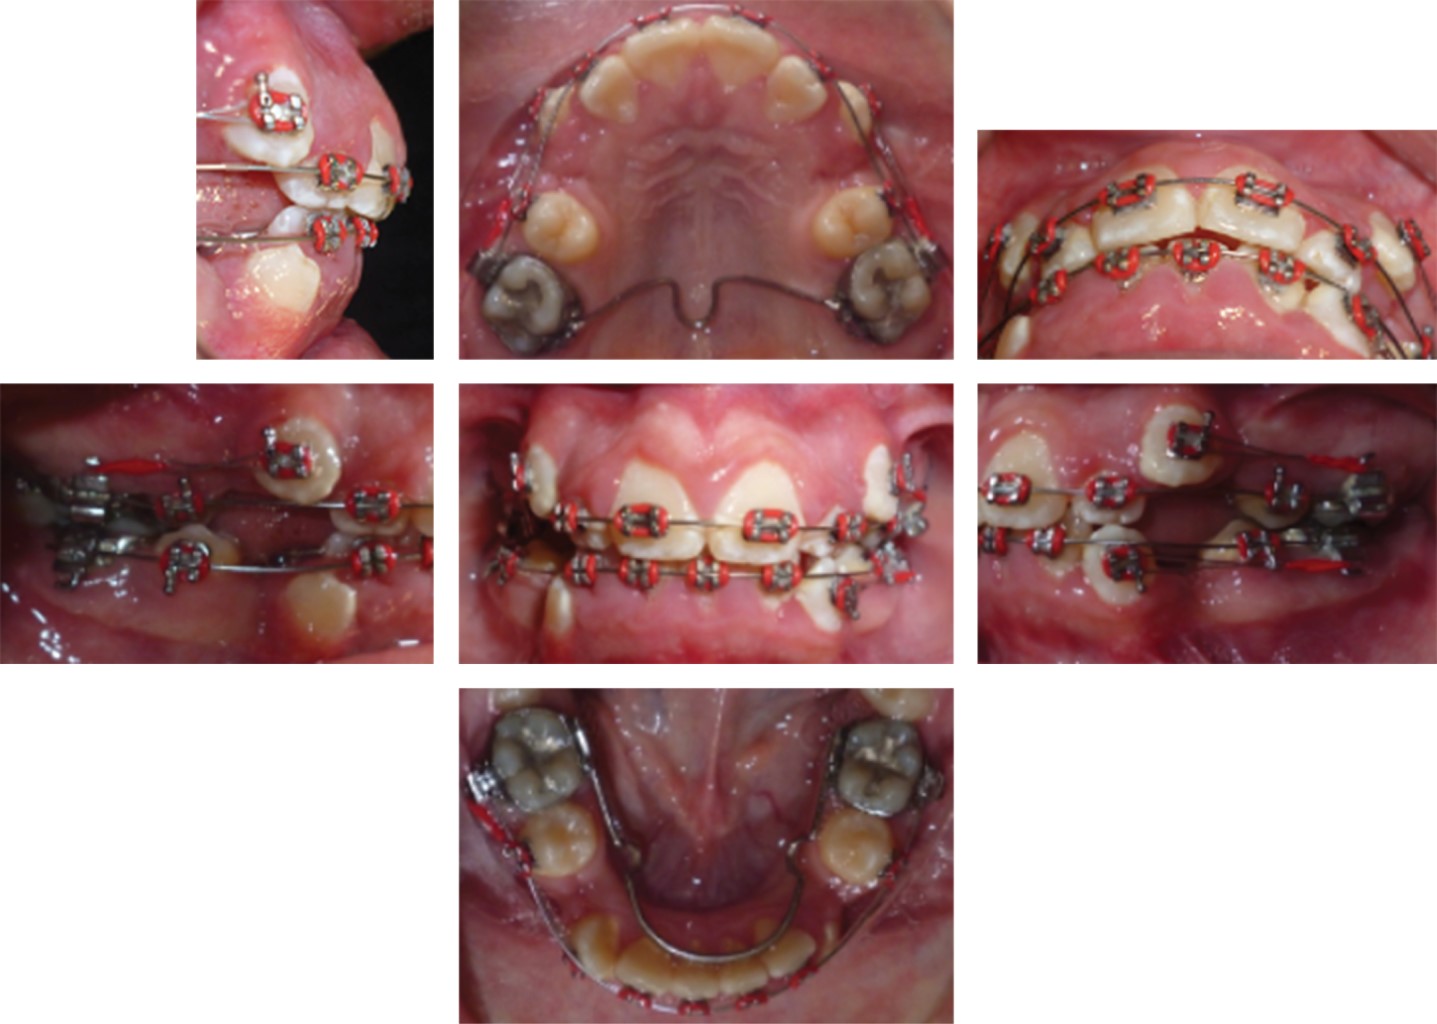

Al examen clínico la paciente presentó desarrollo normal, con un biotipo dolicofacial, perfil convexo, tercio inferior aumentado, línea media facial coincidente con línea media dental (Figura 1). En el análisis intraoral se observó clase I molar, clase canina no establecida por caninos superiores ectópicos, mordida cruzada posterior unilateral derecha, incisivos inferiores proinclinados y protruidos, forma de arco superior triangular e inferior ovoide, línea media inferior desviada 2 mm a la izquierda, sobremordida horizontal 3 mm y vertical 3.5 mm (Figura 1), discrepancia de longitud de arco maxilar de -9.8 mm y mandibular de -10.9 mm, curva de Spee de 2 mm (Figura 2). Radiográficamente se observó dentición permanente, cornetes semipermeables, asimetría de cóndilos, presencia de germen de terceros molares y premolares inferiores sin cierre apical. En la radiografía lateral de cráneo se observaron vías aéreas permeables e incompetencia labial (Figura 3). Se realizó el trazado cefalométrico de Steiner con el software Dolphin 9.0 y se resolvió en una clase II esqueletal con posterorrotación mandibular (Tabla 1). El análisis funcional no presentó alteraciones en la articulación temporomandibular ni hábitos.

En la fase de alineación y nivelación: se utilizaron arcos 0.016" térmico, 0.016" SS, 0.016" × 0.022" térmico. Trabajo: arcos 0.016" × 0.022" SS, 0.017" × 0.025" SS. Se realizó la retracción de caninos superiores e inferiores con retroligadura (Figura 4). Se cerraron los espacios con cadena, se corrigió la línea media y se coordinaron los arcos.

Figura 1

Figura 2

Figura 4

Figura 5